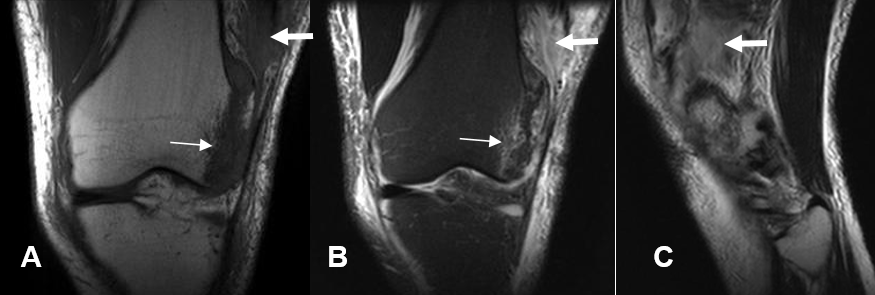

Fig 25 B. Ruptura muscular.

A: RM coronal en T1, B: RM coronal en STIR y C: RM sagital en T2. Paciente con trauma directo, en la rodilla. Se aprecia solución de continuidad en las fibras del músculo recto lateral, las cuales son hipointensas en T1 e hiperintensas en STIR y T2, por ruptura muscular.(Flechas gruesas). Igualmente hay cambios inflamatorios en los tejidos blandos y contusión ósea del cóndilo femoral lateral. (Flechas delgadas).